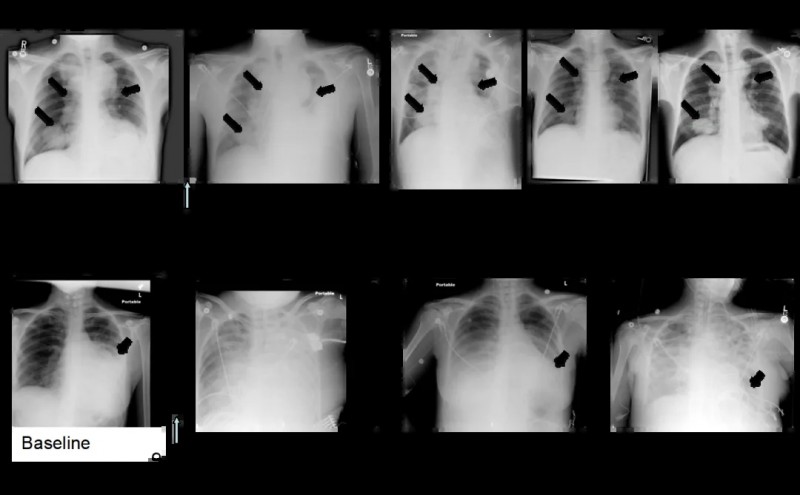

结果显示:69%(9例)患者出现肿瘤消退迹象;在10例可评估疗效的患者中,8例于治疗第30天通过PET扫描或体检观察到初始抗肿瘤活性证据(详见下图)。

▲图源“Clin Cancer Res”,版权归原作者所有,如无意中侵犯了知识产权,请联系我们删除

此外,两例治疗前出现急性呼吸窘迫不良事件的患者(F5-12、F5-14),经TCR-T+DC癌症疫苗联合治疗后,胸部X光片显示,患者肺转移灶随时间推移逐渐缩小(详见补充图7)。